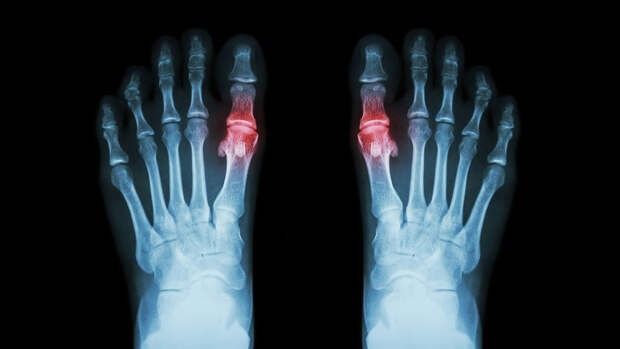

Подагра является наиболее распространенным видом воспалительного артрита, вызванного отложениями в суставах солей мочевой кислоты. Заболевание сопровождается нестерпимой, быстро нарастающей и проходящей за несколько часов или суток болью в суставах, при этом кожа над ними краснеет, а сами они увеличиваются в объёме. Из других симптомов — повышенная температура тела, слабость, потливость. В запущенных случаях на суставах могут образовываться наросты.

"Раньше подагру называли "болезнью королей" и связывали со злоупотреблением красного мяса и алкоголя. Однако XXI век внес свои коррективы в диетические причины подагры, а именно, дополнив список повышенным потреблением рыбы и подслащенных сахаром соков и других напиктов, а также рафинированых злаков. Чтобы снизить риски развития болезни нужно придерживаться здоровой растительной диеты, то есть употреблять цельнозерновые продукты, чай и кофе, а также маложирные молочные продукты. Рыбу, богатую омега-3 жирными кислотами, тоже можно употреблять в умеренных количествах. Здоровая растительная диета, богатая клетчаткой, помогает справиться с хроническим воспалением", – рассказала Дианова.